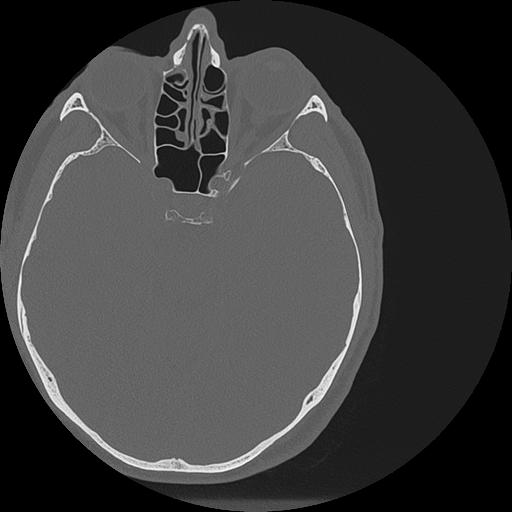

7 HUESO,,Vol,0.5,HUESO,,